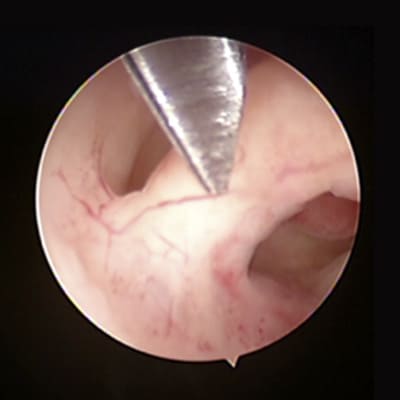

Mioma submucoso